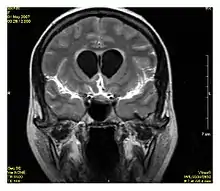

Neuroimaging

MRI is the investigative tool of choice for neurological cancers over CT, as it offers better visualization of the posterior cranial fossa, containing the brainstem and the cerebellum. The contrast provided between grey and white matter makes MRI the best choice for many conditions of the central nervous system, including demyelinating diseases, dementia, cerebrovascular disease, infectious diseases, Alzheimer's disease and epilepsy.[26][27][28] Since many images are taken milliseconds apart, it shows how the brain responds to different stimuli, enabling researchers to study both the functional and structural brain abnormalities in psychological disorders.[29] MRI also is used in guided stereotactic surgery and radiosurgery for treatment of intracranial tumors, arteriovenous malformations, and other surgically treatable conditions using a device known as the N-localizer.[30][31][32] New tools that implement artificial intelligence in healthcare have demonstrated higher image quality and morphometric analysis in neuroimaging with the application of a denoising system.[33]